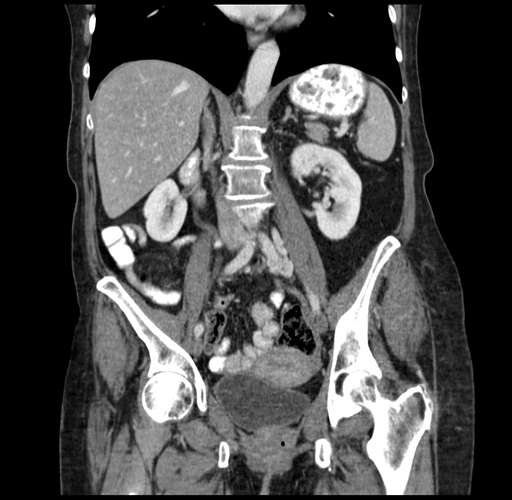

Coronal Venous